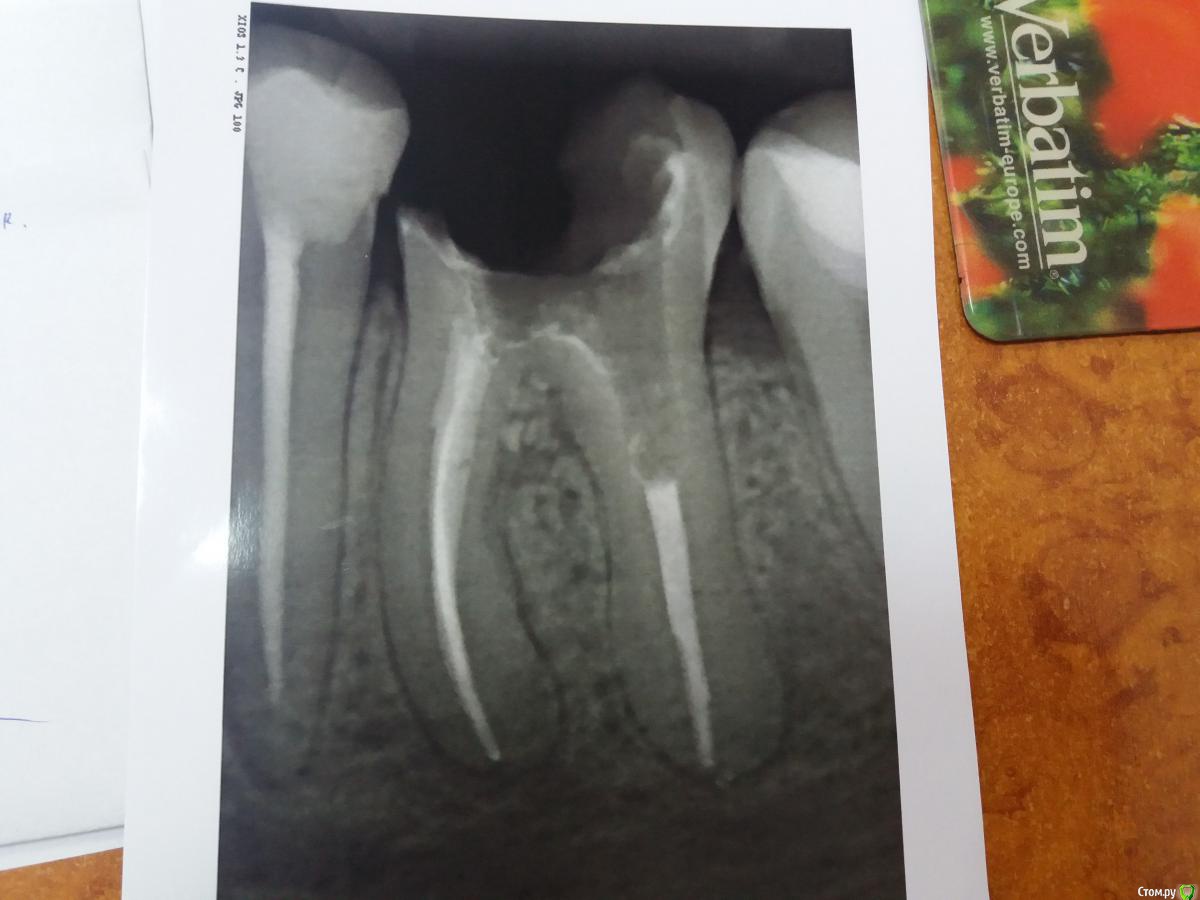

Moraine Опубликовано 19 июня, 2018 Поделиться Опубликовано 19 июня, 2018 (изменено) Здраствуйте, прошу помощи и совета специалистов, поскольку мнения розходятся. Ситуация - на снимках- первый - зуб 36 ( шестерка левая нижняя) сейчас- второй - зуб 46 ( шестерка правая нижняя) сейчас -третий - 36 на етапе подготовки под штифт После пломбирования каналов обратилась к ортодонту - ставить коронки - он мне поставил штифты металличиские ( на снимках).Потом на 36 ( левый) поставили коронку, но сразу же ( на протяжении 1,5 дня) у меня началось воспаление, пришлось коронку снять, сказал ждать 10 дней, и может надо будет зуб вырвать. Сейчас десна немного воспалены, сказал доктор полоскать содой и йодом. К правому воспросов у него нет и он меня не беспокоит, но тоже ждем ещё несколько дней , чтоб поставить коронку. Я обратилась за консультацией ещё в одну клинику, но там сказали что оба зуба надо удалить, и что шрифты установлены неверно. С их слов, спасти зубы шансов нет, из-за действий с штифтом, теперь только импланты. Я теперь не знаю, что думать. Выходит, что мне испортили зубы. на коротые при грамотном подходе можно было поставить коронки? Или в другой клинике очень радикально подходят к вопросу? Прошу озвучить Вашее профессиональное мнение - действительно ли критически неверно установлен штифт и какие шансы спасти зубы? А также какие риски при установленни коронки на 46? Благодарю заранее за помощь. Изменено 19 июня, 2018 пользователем Moraine Ссылка на комментарий

Дмитрий Л. Опубликовано 19 июня, 2018 Поделиться Опубликовано 19 июня, 2018 +1 но если как можно быстрее удалить штифты и запломбировать дно зуба то есть небольшой шанс спасти. Правда вменяемый врач пойдёт по этому пути если вы четко поймёте что такое лечение может быть безуспешным и возьмёте ответственность на себя. Выжидательная тактика или полоскания себя не оправдают. 1 Ссылка на комментарий